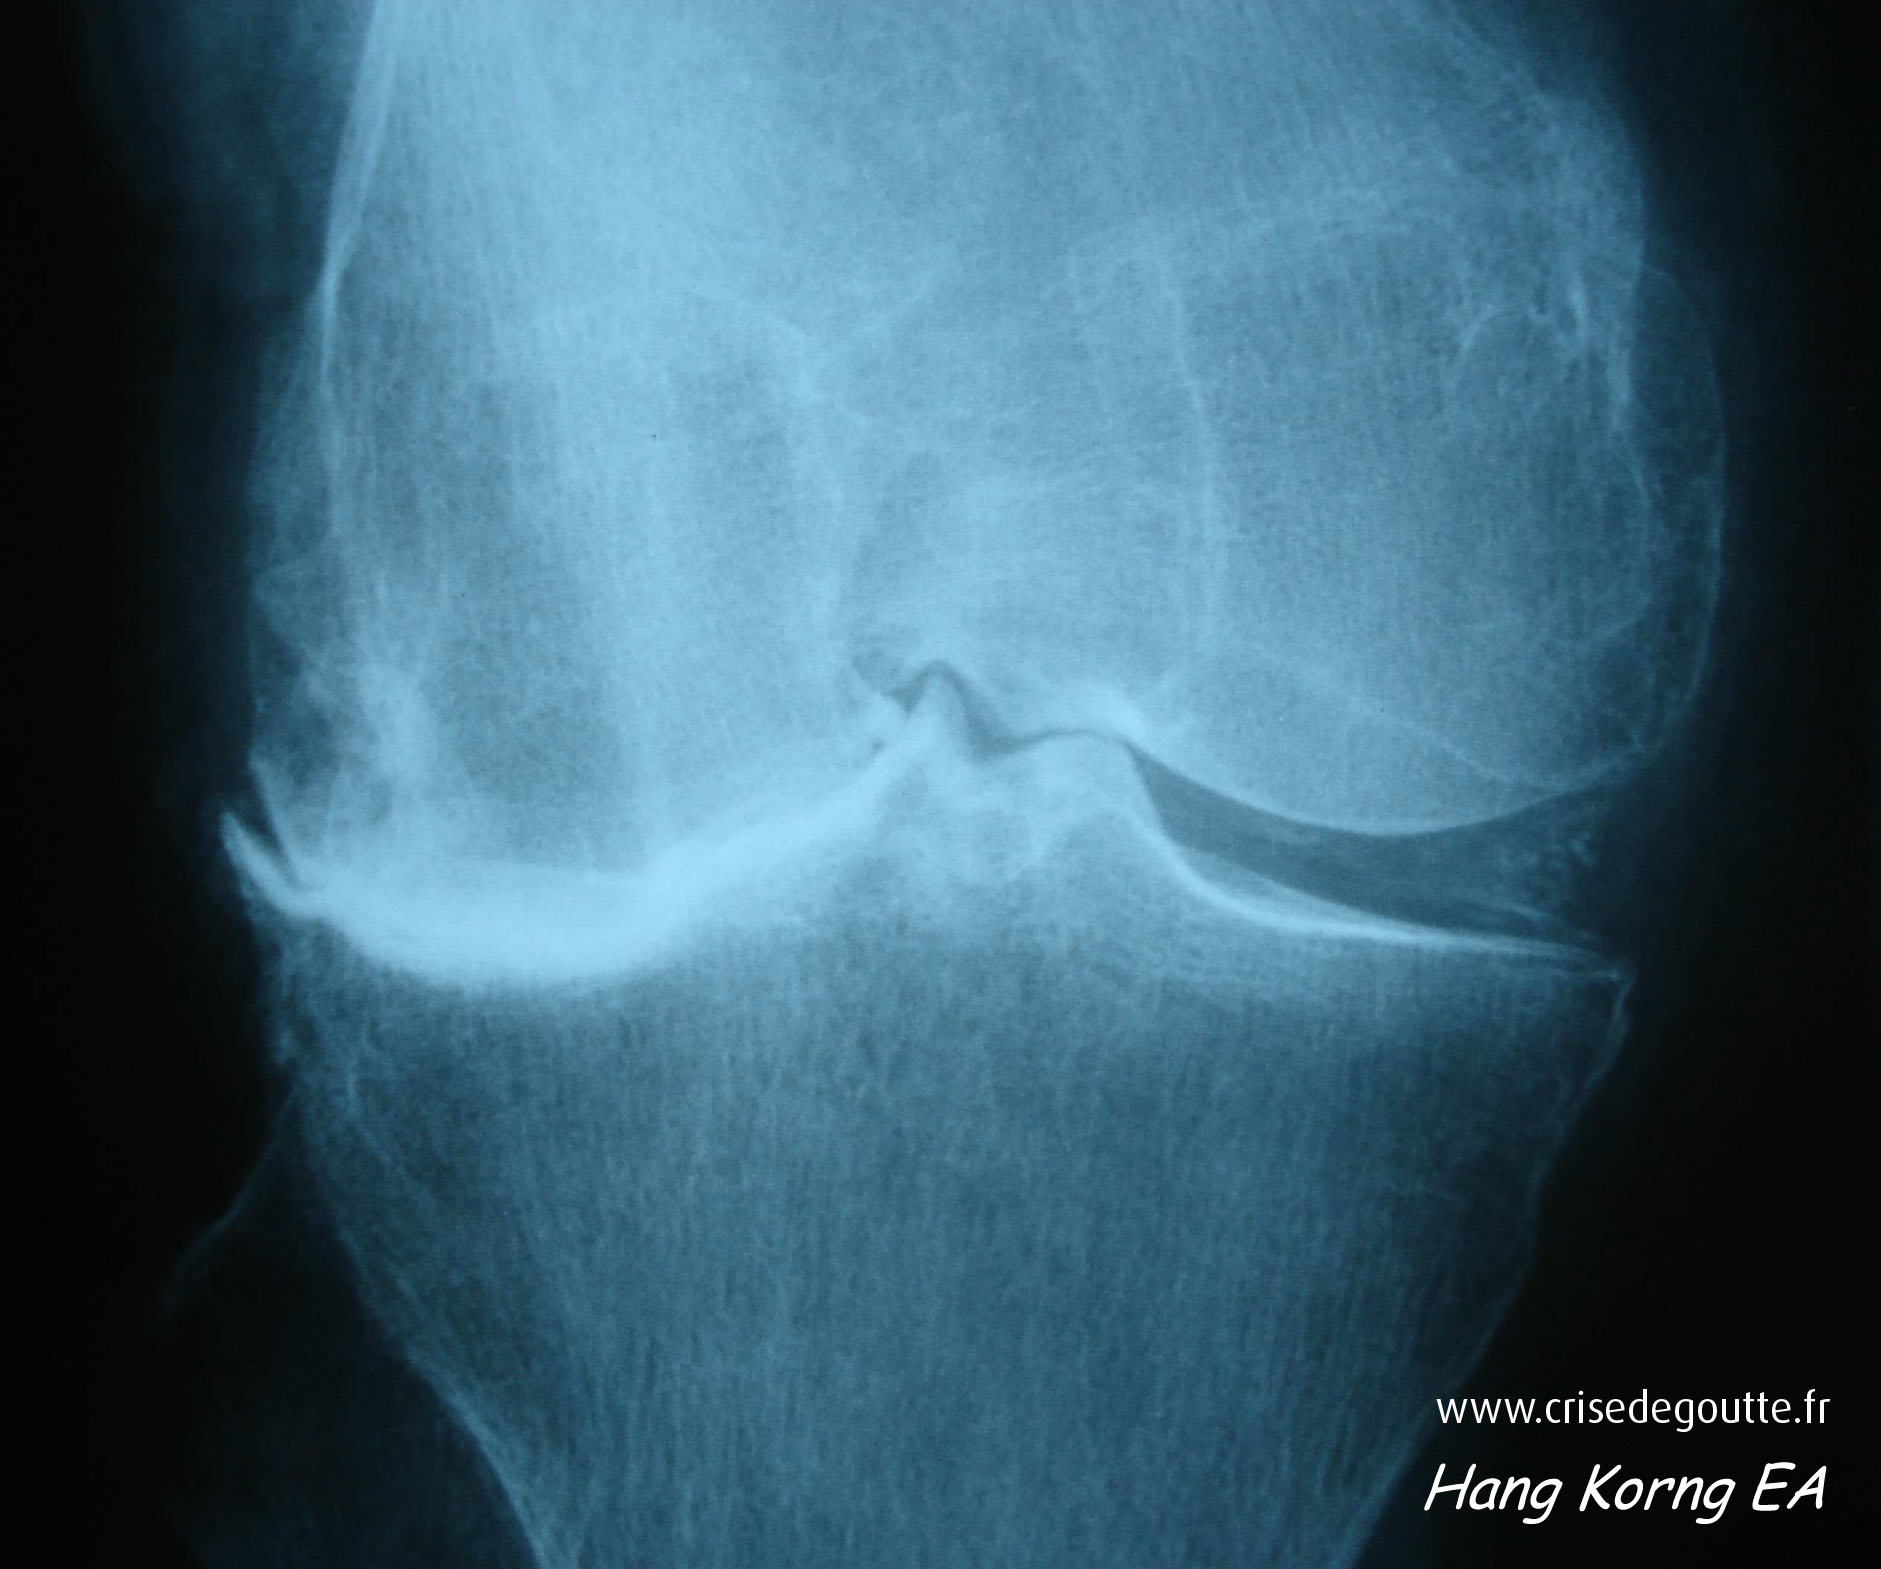

Imagerie

PPCD